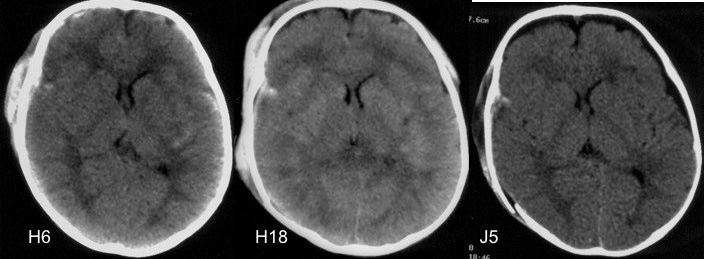

s’agissant d’un accident à haute cinétique, on rencontre souvent des lésions encéphaliques diffuses

chez le nourrisson, on rencontre des hématomes sous-duraux se constituant en quelques jours, ressemblant à celui du bébé secoué, mais avec en plus des signes d’impact.

Infantile Subdural Hematomas Due to Traffic Accidents

Pediatr Neurosurg. 2002 Nov;37(5):245-53